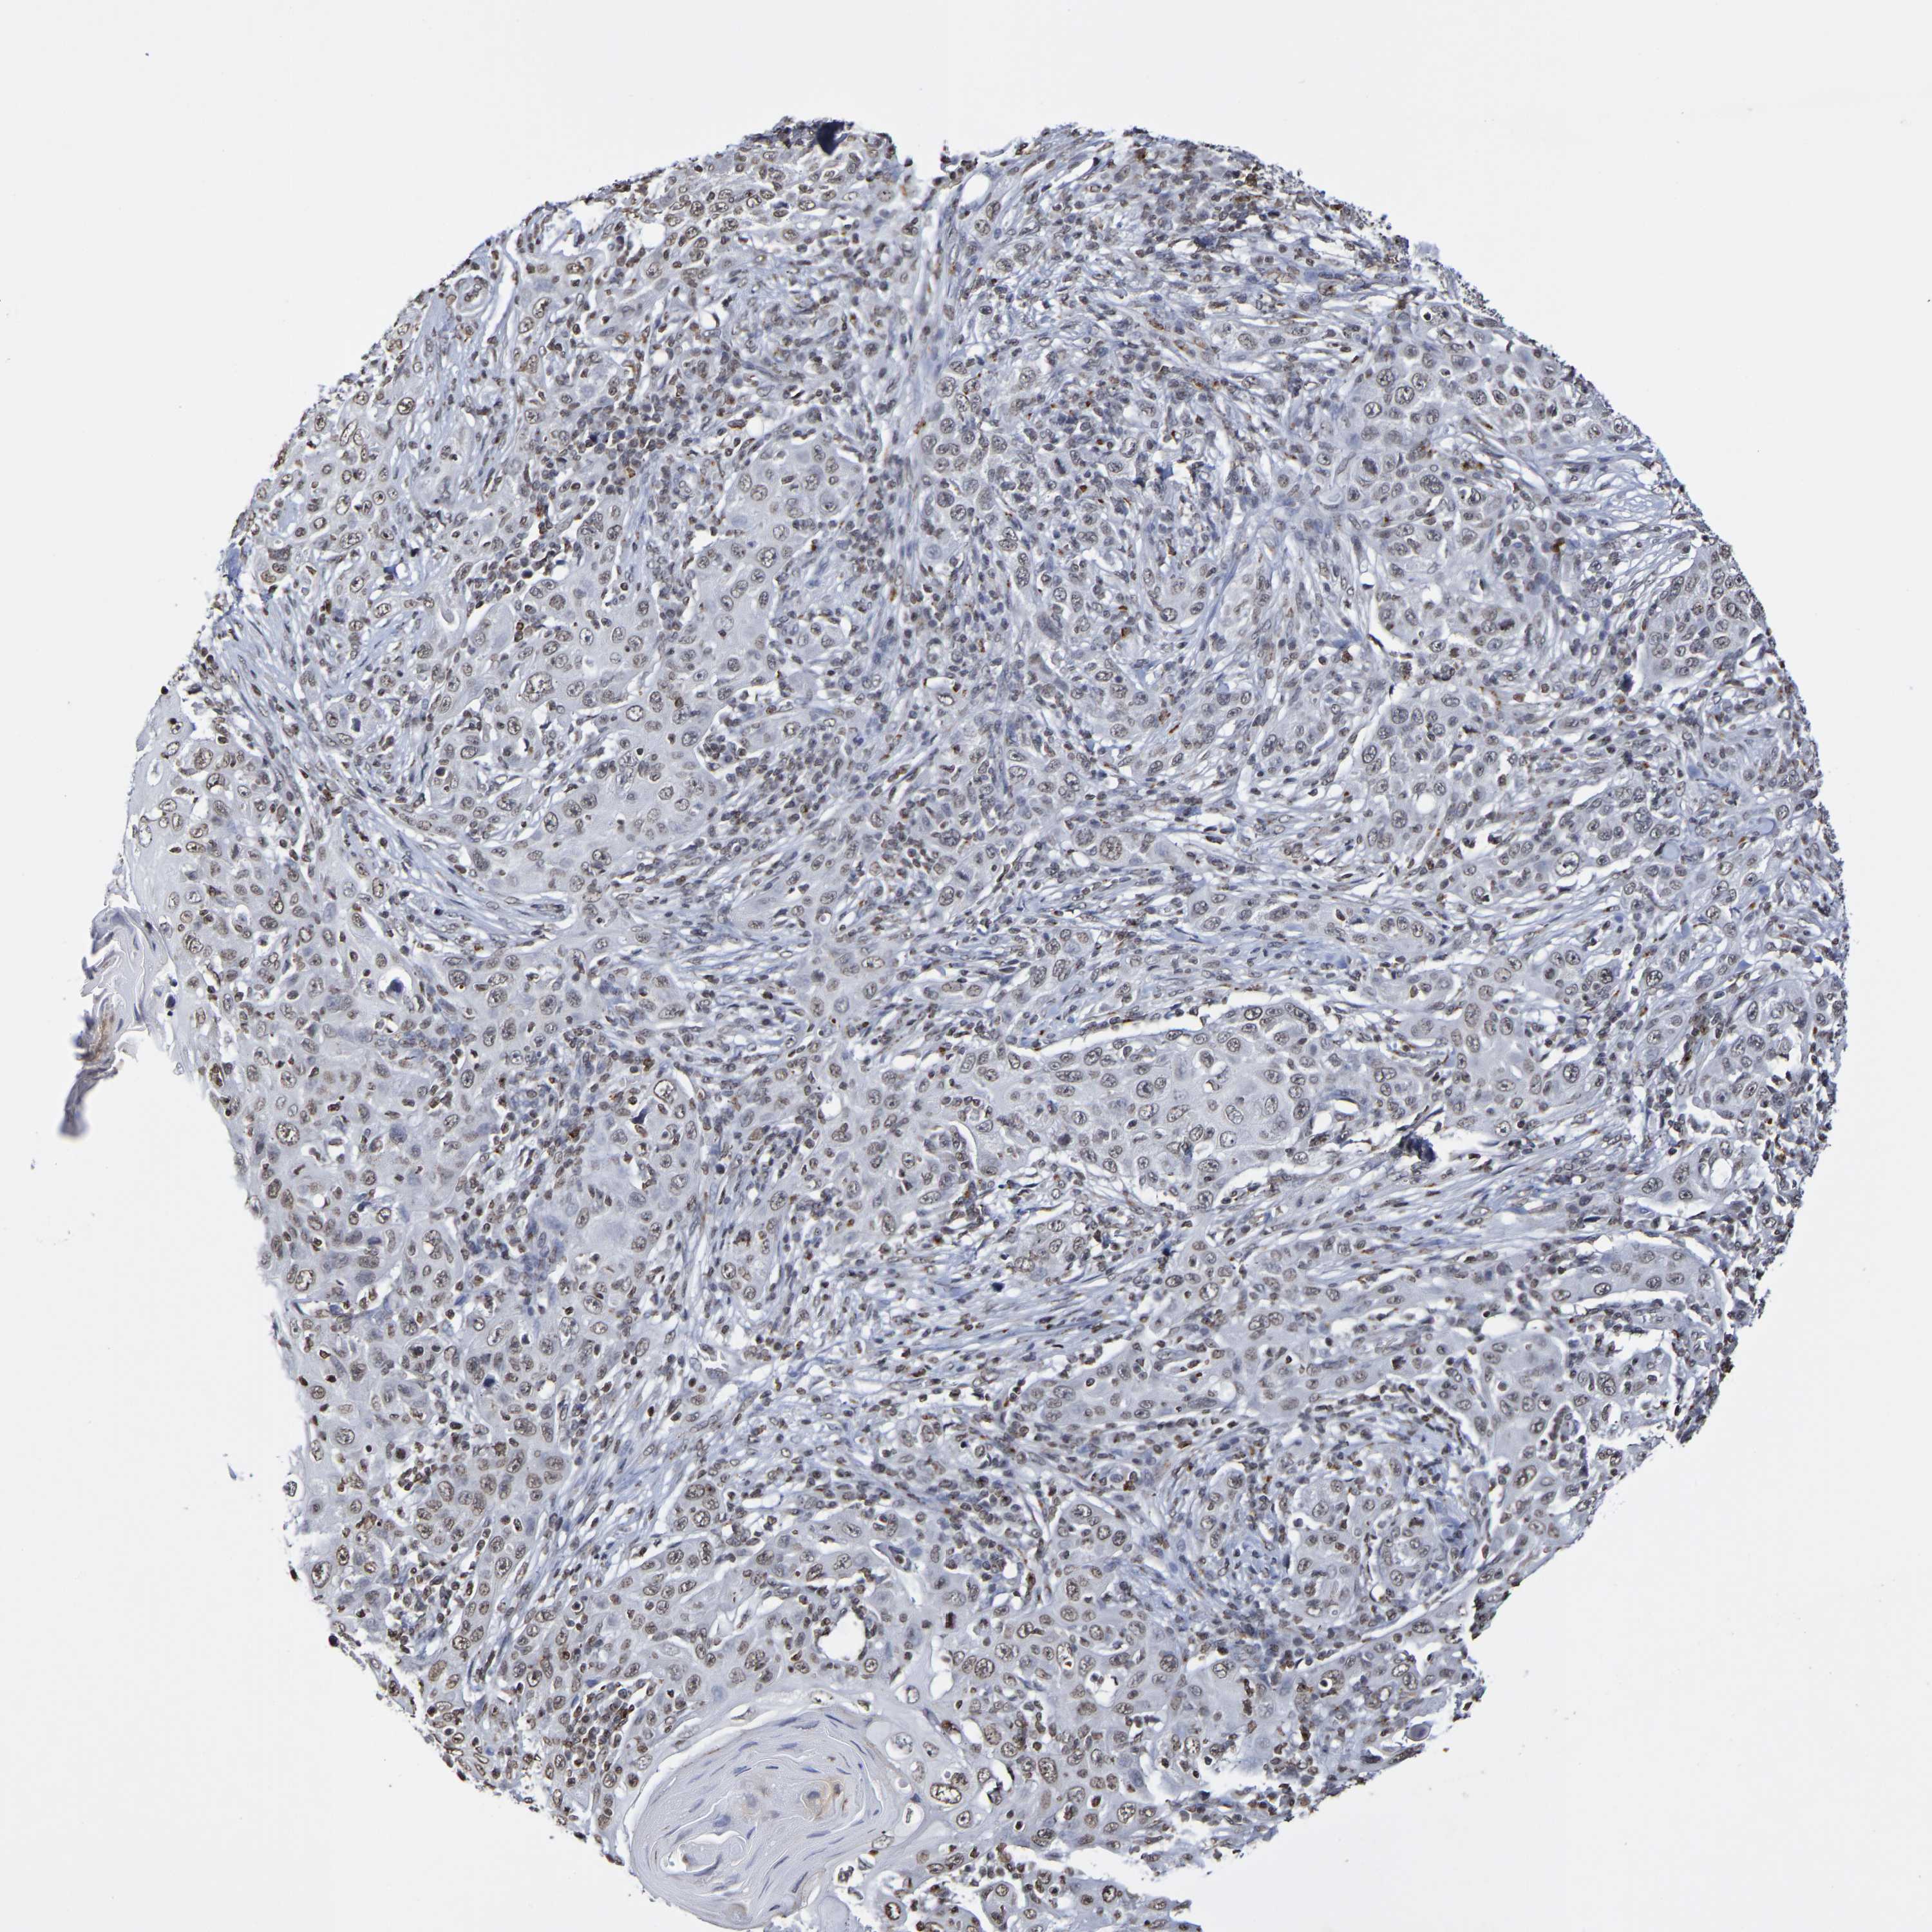

SKIN CANCER - Protein expressioni

A mouse-over function shows sample information and annotation data. Click on an image to view it in a full screen mode. Samples can be filtered based on level of antibody staining by selecting one or several of the following categories: high, medium, low and not detected. The assay and annotation is described here.

Note that samples used for immunohistochemistry by the Human Protein Atlas do not correspond to samples in the TCGA dataset.

Antibody stainingi

Antibody staining in the annotated cell types in the current human tissue is reported as not detected, low, medium, or high, based on conventional immunohistochemistry profiling in selected tissues. This score is based on the combination of the staining intensity and fraction of stained cells.

Each image is clickable and will lead to virtual microscopy that enables deeper exploration of all samples and also displays staining intensity scores, fraction scores and subcellular localization as well as patient and tissue information for each sample.

Antibody CAB011596

Staining

High

Medium

Low

Not detected

Intensity

Strong

Moderate

Weak

Negative

Quantity

>75%

75%-25%

<25%

None

Location

Nuclear

Cytoplasmic/membranous

Cytoplasmic/membranous,nuclear

Click images for details